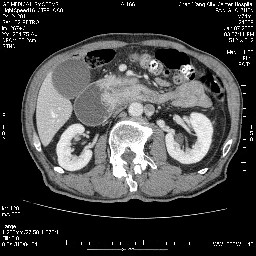

今日手术结果:胰腺钩突癌侵犯十二直肠,腹腔淋巴结转移.

病变考虑为钩突癌。

病变主要位于钩突(癌)。如是壶腹部,肝内外胆管扩张明显。